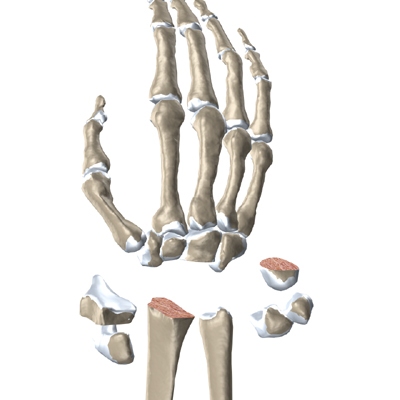

The wrist is made up of eight separate small bones, called the carpal bones. The carpal bones connect the two bones of the forearm, the radius and the ulna, to the bones of the hand. The metacarpal bones are the long bones that lie mostly underneath the palm. The metacarpals are in turn attached to the phalanges (the bones in the fingers and thumb).

Modern artificial wrist joints are made of metal and plastic. The part that fits against the end of the radius bone of the forearm is called the radial component. It is made up of two pieces. A flat metal piece is placed on the front part of the radius. It has a stem that attaches down into the canal of the bone. A plastic cup fits onto the metal piece, forming a socket for the artificial wrist joint.

The part that replaces the small wrist bones is called the distal component. This piece is made completely of metal. It is globe shaped to fit into the plastic socket on the end of the radius. The metal distal component is attached by two metal stems that fit into the hollow bone marrow cavities of the carpal and metacarpal bones of the hand.

The surgeon needs to make room for the artificial joint. To do this, most of the first row of:

Carpal Bones are Removed

from the wrist. The end of the radius is also shaped to fit the prosthesis.